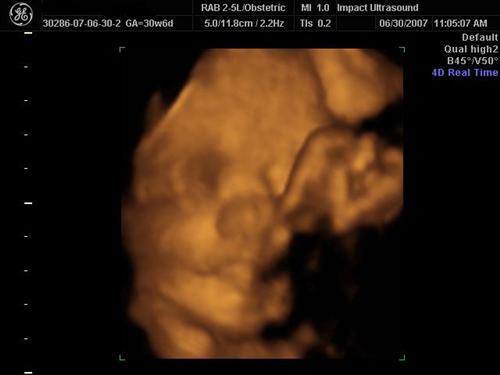

We went to Impact Medical Technologies today for our 3D/4D sono! It was alot of fun! Our normally sleepy, non-cooperative baby was awake and soooo active the entire time! They got some really great shots of her! Here are a few!